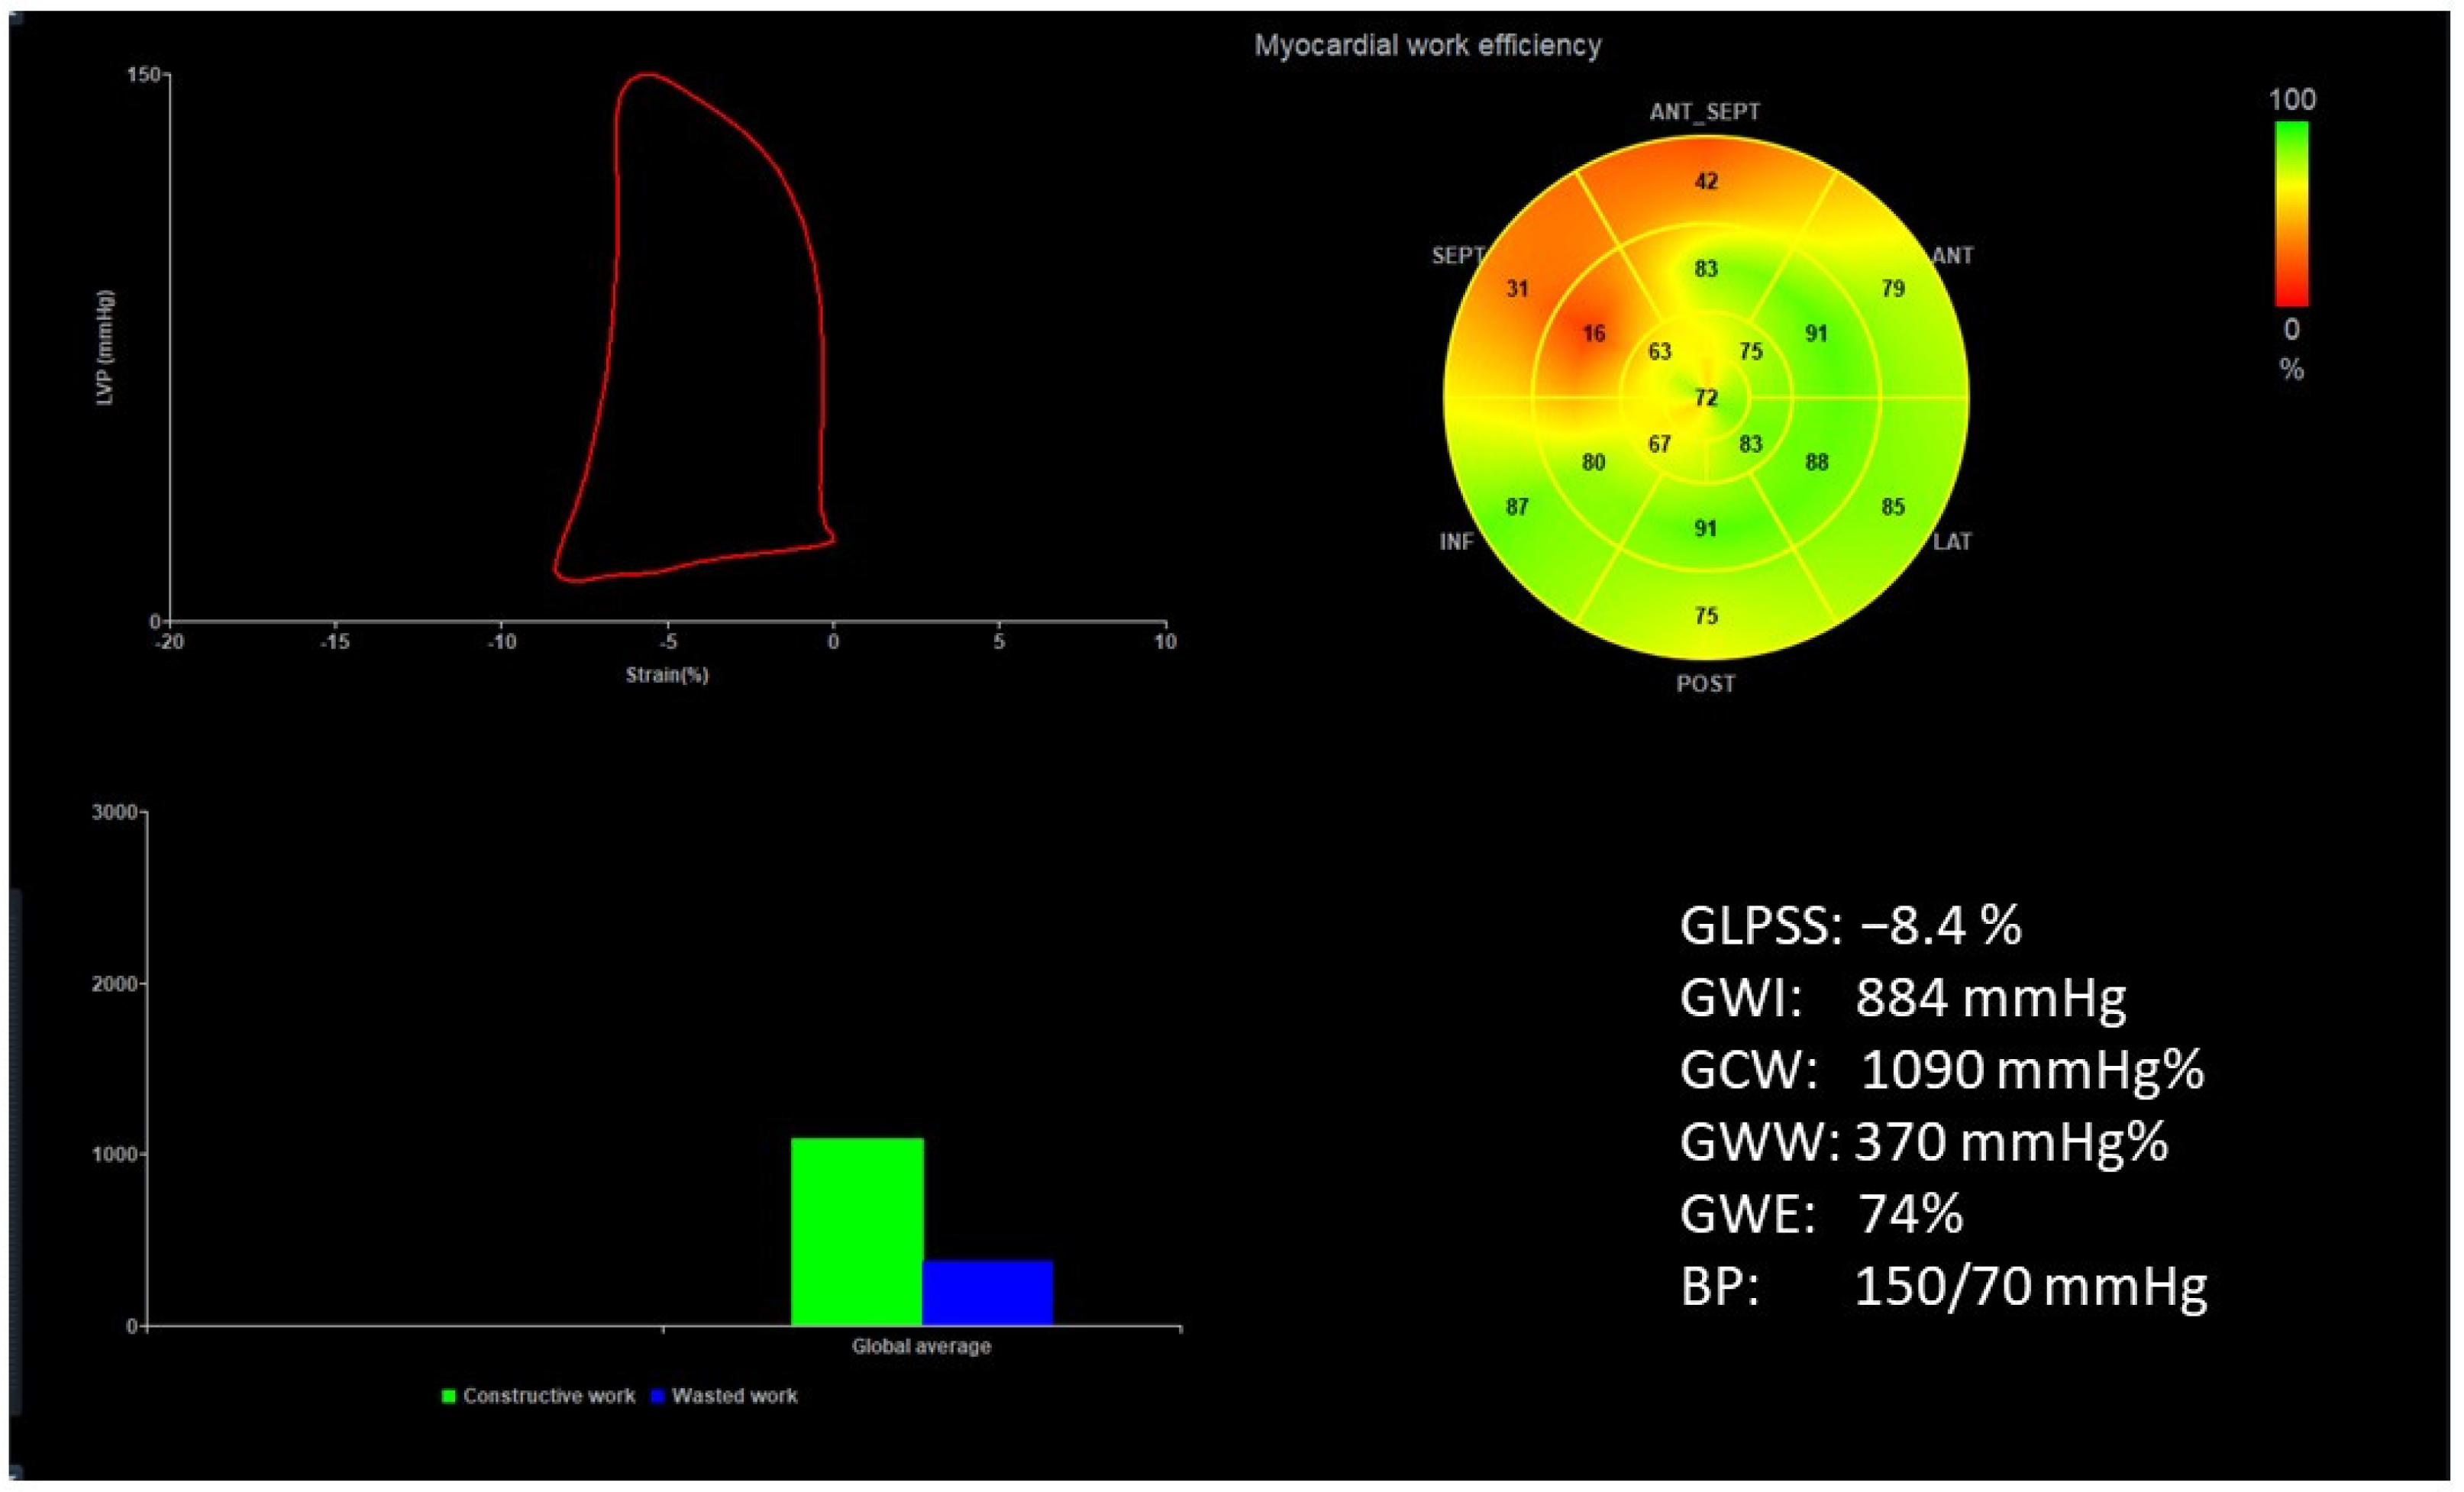

Figure 1 and Figure 2 show two contrasting examples (a healthy person and a patient after myocardial infarction and left bundle branch block) of STE curves with GLPSS, LVEF and LV pressure–strain loops and results of GWE for all LV segments.

Figure 2.

An example of echocardiography of a 61-year-old man with the left bundle branch block and a history of myocardial infarction. A set of individual longitudinal strain curves for all segments shown in different colors, with the average curve shown as a white dotted line, a bull’s eye of segmental longitudinal peak systolic strains and a summary of global longitudinal peak systolic strain (GLPSS) are shown in the top panel. The LV pressure–strain loop with the bull’s eye representation of myocardial work efficiency for each of the segments and a summary of all myocardial work indices are shown in the lower panel. Abbreviations: GLS—global longitudinal peak systolic strain, EF—ejection fraction, GWI—global myocardial work index, GCW—global constructive work, GWW—global wasted work, GWE—global work efficiency, BP—blood pressure.